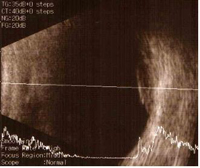

초음파의 파형을 통해 종양의 외부 전이나 두께, 높이 등을 파악할 수 있으며 환자가 거의 불편함 없이 검사를 받을 수 있습니다.

[ 안구 초음파 소견 ]